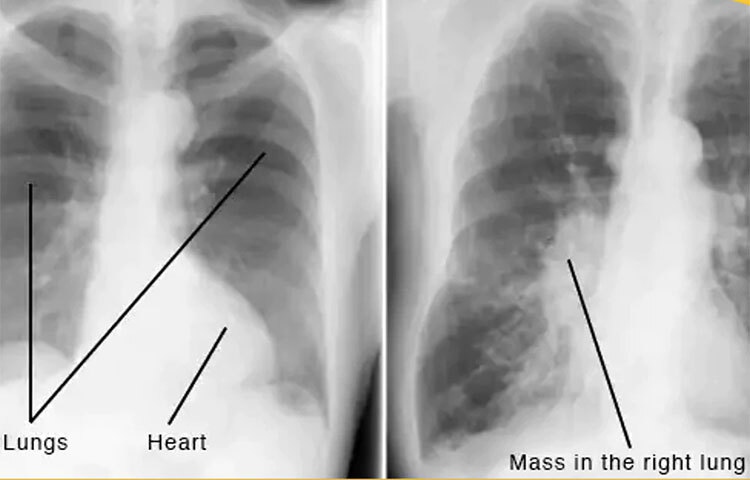

চিকিৎসকরা বারবার ধূমপান ছেড়ে দেওয়ার কথা বললেও যারা এখানো ধূমপান করছেন, পাশাপাশি যারা বেশি পরিমাণে ধূমপান করেন তাদের বছরে অন্তত একবার কিছু পরীক্ষা আছে তা করানো উচিত। জেনে নিন কোন কোন পরীক্ষাগুলো করাতে হবে।